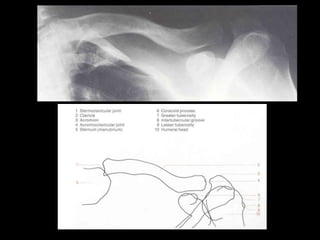

This document provides an overview of normal musculoskeletal imaging. It discusses basic x-ray concepts and densities. It then reviews normal anatomy as seen on x-rays of the skull, spine, pelvis, chest, and extremities. Key anatomical structures are labeled on example x-rays for the shoulder, hip, knee, and foot. Quizzes are included to test recognition of anatomical structures and patient age based on x-rays.